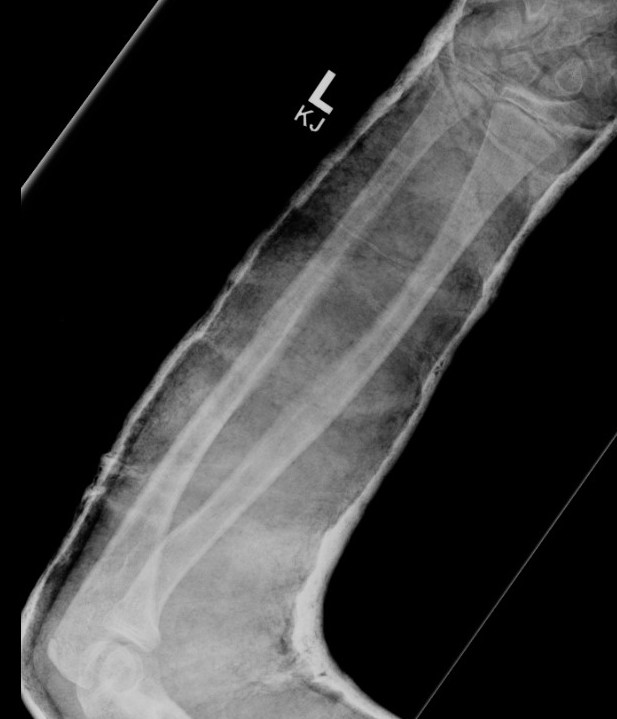

3. Intramedullary elastic nail

- smaller scars with insertion

- easier to remove than plates

Disadvantage

- generally immobilized

- must be removed

- non anatomical reduction compared with plates with theoretical risk of loss supination / pronation

- risk of extensor tendon rupture due to prominence of nails at insertion sites

TENS technique

Technique

Radius (typically first as more difficult to reduce)

Entry point with awl 2 cm proximal to distal physis

1. Radial styloid / distal lateral entry

- ensure radial nerve / cephalic vein, 1st extensor compartment protected

2. Listers tubercle / dorsal entry

Elastic Nail size

60 - 70% of the intramedullary canal

Typically 1.5 - 2.5 mm

Fracture reduction

Avoid passing nails incorrectly multiple times as may cause compartment syndrome

Bend tip of elastic nail

May need small open reduction

Cut nail

Withdraw 1 cm, cut with endcutter, then advance

Ulna (usually reduced after radius fixation)

Entry point 2 cm distal to apophyseal plate

1. Proximal lateral

- avoids ulna nerve

3. Distal medial

Postoperative

Cast in supination to tighten interosseous membrane

Cast 6 weeks

Removal of TENS at 4 - 6 months once osseous union established